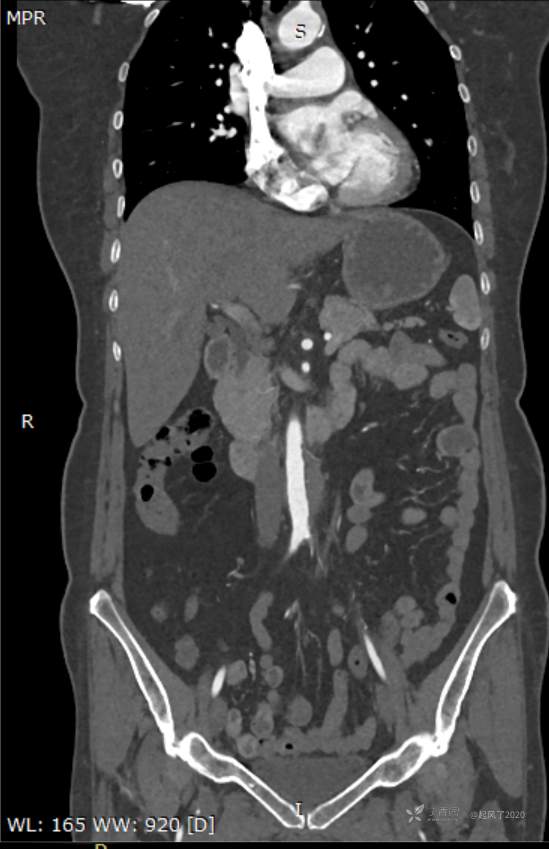

求助 | 女,61岁,下腹部、腰及双髋关节隐痛1月余

II型糖尿病10年余,既往饮食控制血糖在7~8左右,今年1月份开始服用二甲双胍;2009年4月因“子宫肌瘤、双侧输卵管慢性炎症”行子宫及附件切除术;2021年1月体检发现双侧甲状腺多发结节,较大者12*7mm;高血脂10余年,近1月开始规律服药,控制不理想;无高血压